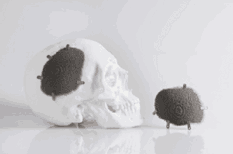

Recientemente se recurrió a Protolabs para apoyar la creación de un implante craneal a medida, trabajando estrechamente con el diseñador para fabricar el implante según los requisitos muy específicos de un paciente, en un plazo de tres días.